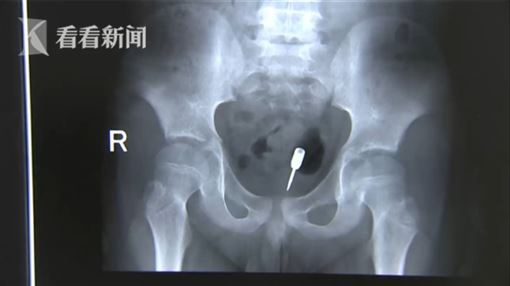

Theo Kankanews, cậu bé được đưa vào cấp cứu tại Bệnh viện Nhân dân Thành phố Hải An trong tình trạng đau thắt ruột. Phim chụp X-quang cho thấy một vật sắc nhọn không xác định ở bụng dưới của cậu bé. Qua thăm khám, các bác sĩ nhận thấy đây là chiếc phi tiêu với đầu là một mảnh kim loại sắc nhọn.

Chiếc phi tiêu với một đầu kim loại nhọn trong bụng của cậu bé 9 tuổi. Ảnh: Kankanews.